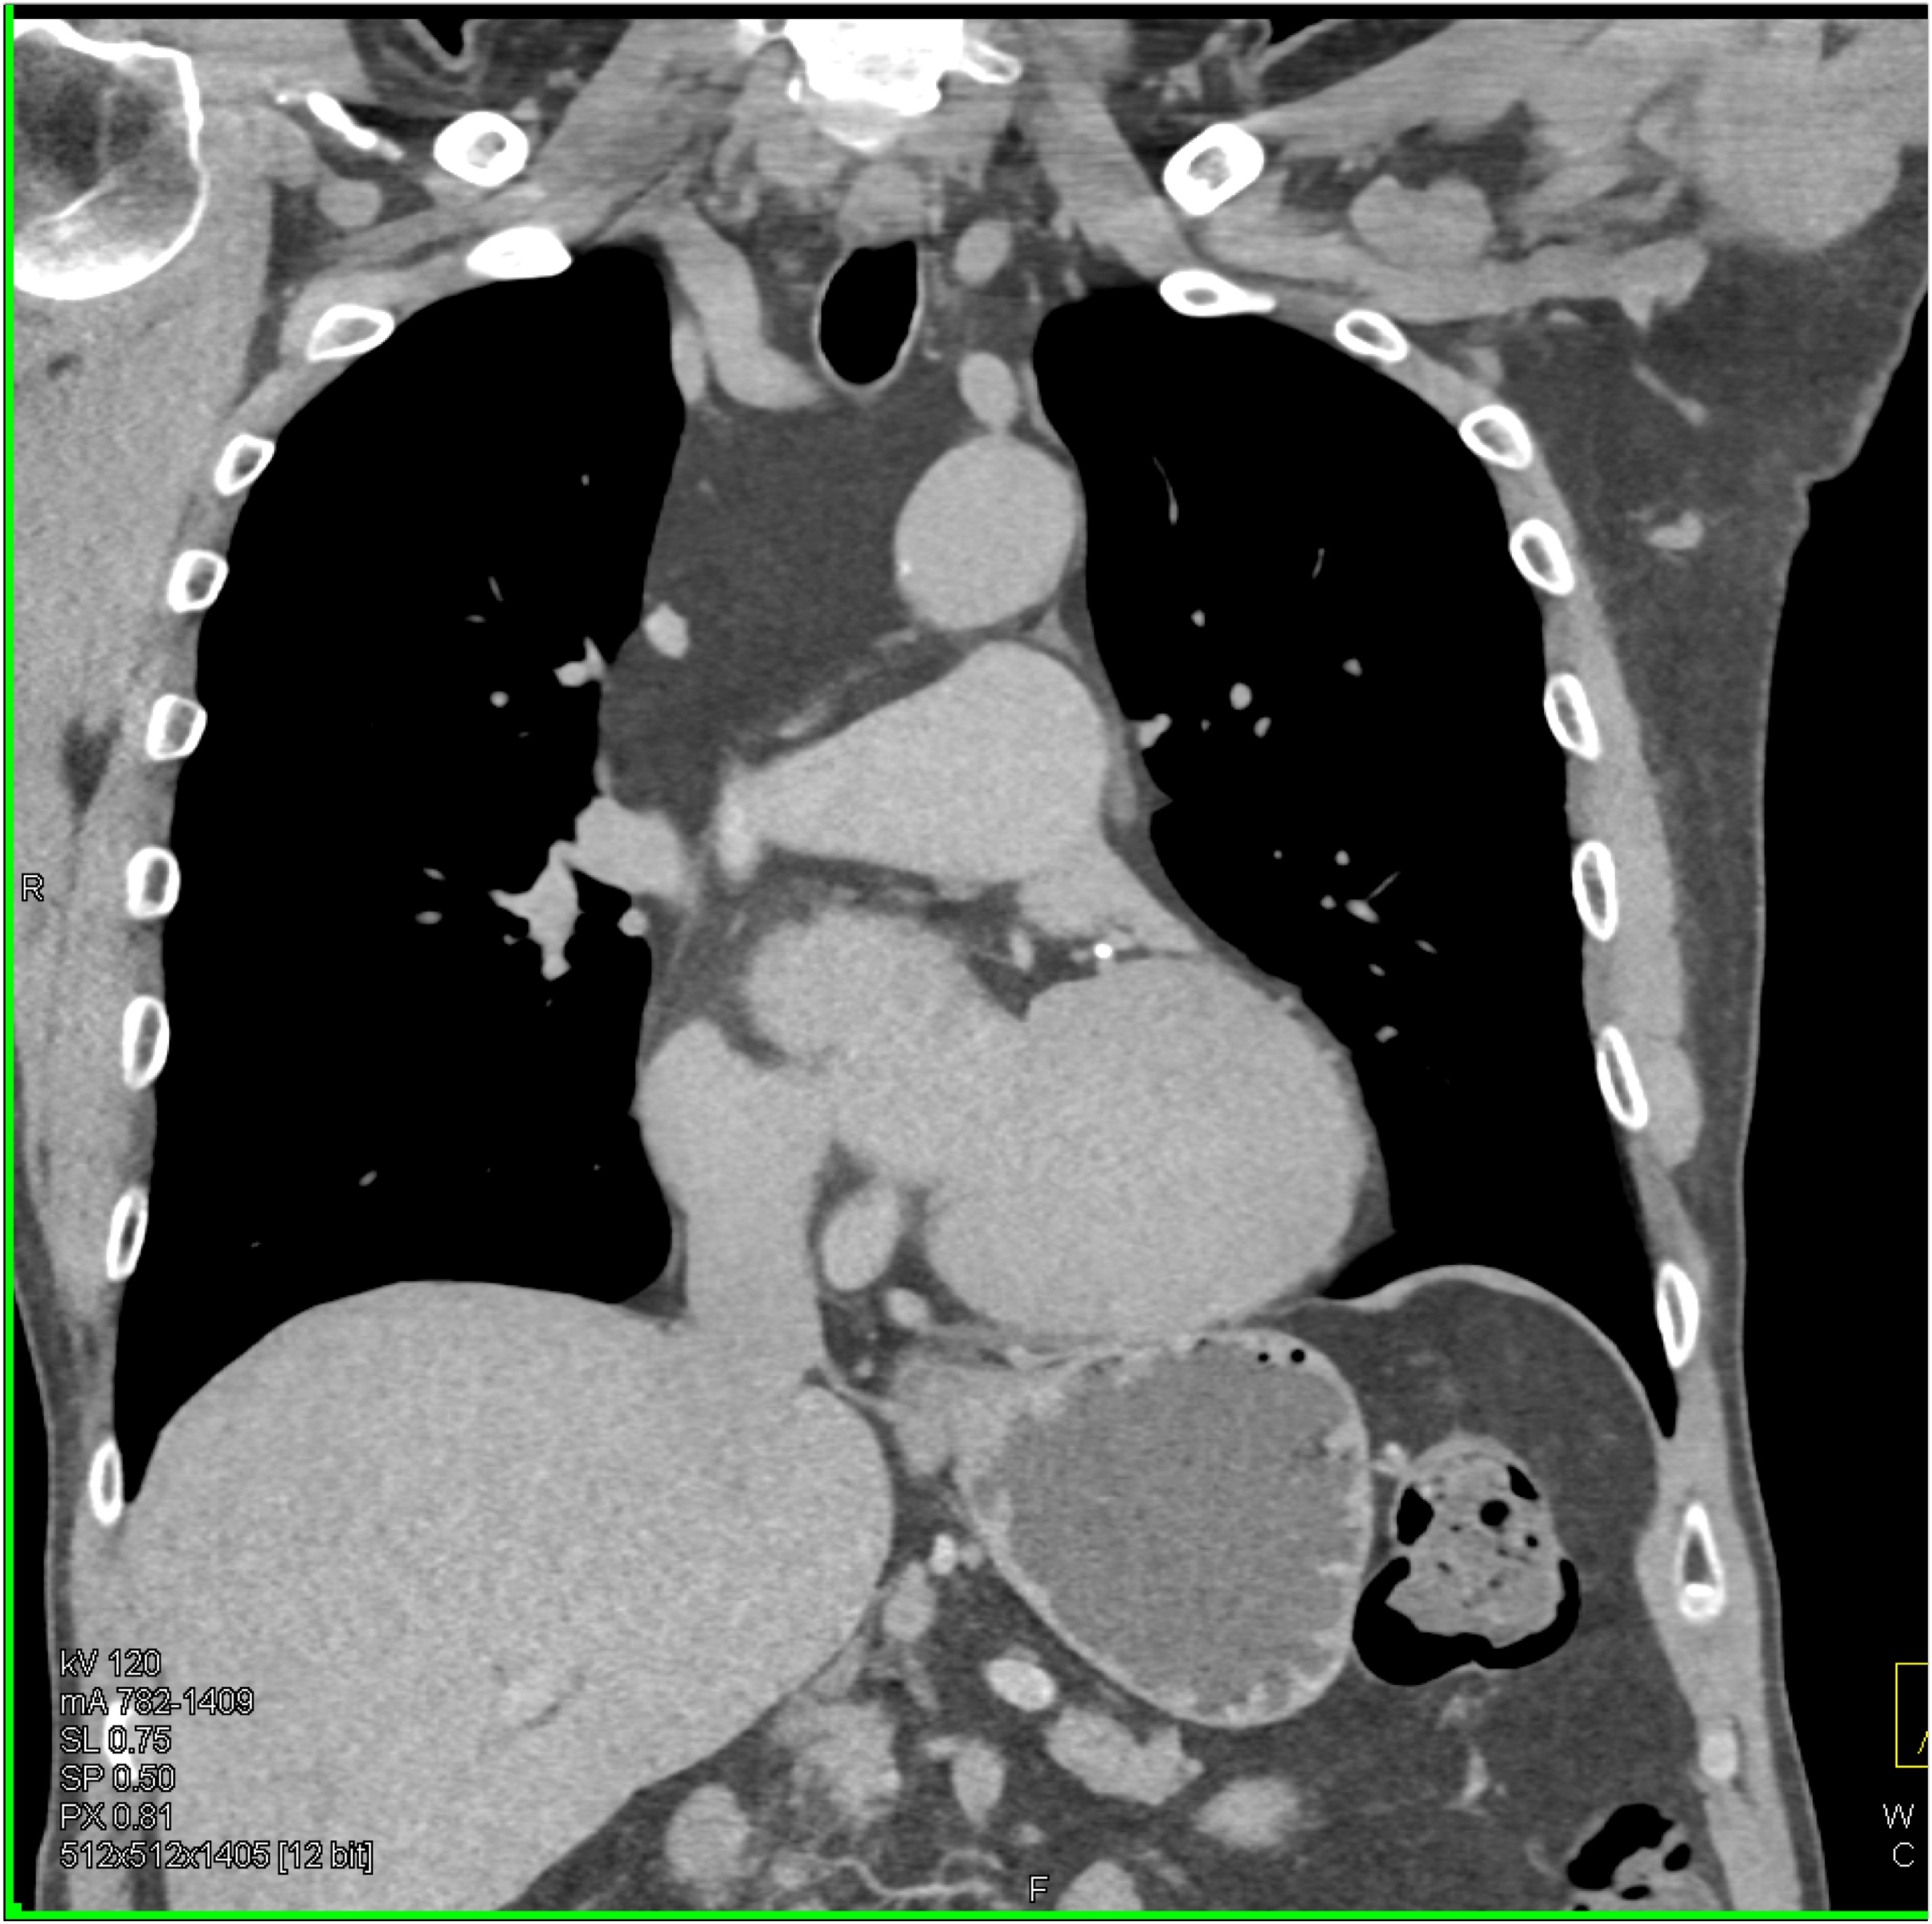

8) In this patient with mediastinal widening on CXR the best diagnosis is?

lymphoma

germ cell tumor

lung cancer

teratoma